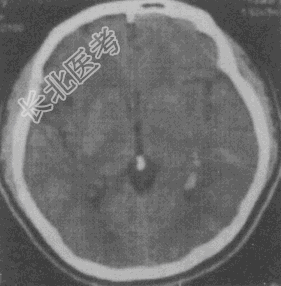

- 单项选择题男性,39岁, "癫痫"发作2次,无发热、肢体活动不适等症状, 根据其CT平扫及强化图像(见图),应首先考虑以下何种诊断

A、星形细胞瘤

B、AVM

C、脑出血

D、脑膜瘤

E、脑梗死